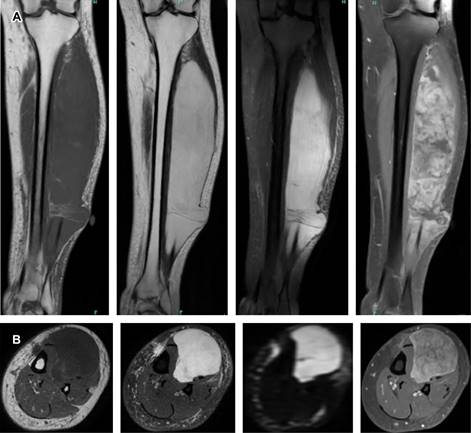

Femenino de 47 años sin antecedentes de importancia, quien presenta tumoración en extremidad inferior izquierda. La RM revela lesión ovoidea en el músculo extensor largo de los dedos y extensor largo del primer dedo, de contenido hiperintenso en secuencia T2 con zona hipointensa central con aparente matriz fibrovascular e importante realce heterogéneo en secuencias ponderadas con medio de contraste altamente sugestivo de fibrosarcoma (Figura 1).

Figura 1: A) Secuencia coronal T1, T2 con suspresión grasa y T1 con suspresión grasa y gadolinio donde se observa en el compartimiento anterior de la pierna izquierda lesión de comportamiento hipointenso e isointenso al plano muscular en T1, hiperintenso en T2 con imágenes lineales y nodulares hipointensas, que al uso de medio de contraste muestra realce heterogéneo con zona central de aparente matriz fibrovascular, que mide 253 × 53 mm. B) Secuencia axial T1, T2 con supresión grasa, disfunción y T1 con gadolinio, donde se corrobora localización en músculo extensor largo de los dedos y extensor largo del primer dedo con aparente delimitación a planos musculares y tejidos blandos adyacentes, que muestra franca restricción a la difusión de moléculas de agua en difusión.

Radiológicamente aparecen como lesiones ovoides, localizadas, con márgenes ligeramente irregulares.1 Suelen localizarse debajo de la fascia profunda y tienden a invadir la superficie, afectando la piel y el tejido subcutáneo. La RM es el estudio de elección para evaluar este tipo de neoplasias, caracterizándose por presentar señal hipointensa en T1, señal heterogénea de baja y alta intensidad en T2 y restricción a la difusión. En la RM contrastada, las lesiones muestran realce periférico heterogéneo o realce con patrón de espiga (altamente sugestivo de un fibrosarcoma adulto).2 La TC evalúa compromiso óseo e identifica áreas en forma de bandas de baja densidad (tabiques fibrosos), signo importante para el diagnóstico correcto de esta entidad.1,2